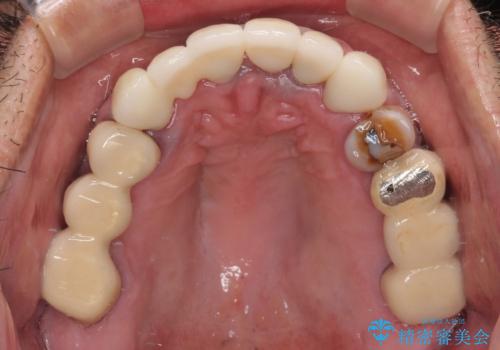

仮歯での期間が長かったとのことでしたが、当院での治療開始後はあっという間に綺麗な前歯に仕上がり、患者様には大変満足していただけました。